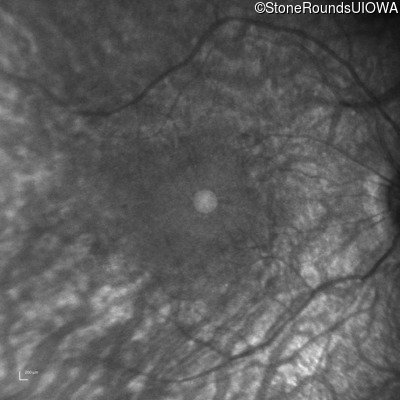

Infrared Fundus Photograph - Right - 20/50

Exemplar